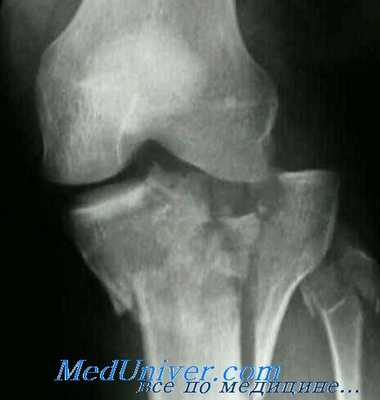

Для выявления этих переломов обычно достаточно снимков в боковой и косой проекциях. Кроме того, для оценки степени вдавления очень информативным может оказаться снимок суставной площадки. Анатомически суставная площадка имеет скос назад и вниз. На рутинных рентгенограммах этот скос не будет заметен, что замаскирует некоторые вдавленные переломы. Проекция суставной площадки компенсирует этот скос и позволит точнее выявить вдавленные переломы суставной площадки. При определении протяженности перелома всегда оказываются полезными рентгенограммы в косых проекциях.

Все рентгенограммы коленного сустава необходимо тщательно просмотреть на наличие отрывных фрагментов головки малоберцовой кости, мыщелков бедра и межмыщелкового возвышения, указывающих на повреждение связочного аппарата. Расширение суставной щели в сочетании с переломом противоположного мыщелка предполагает повреждение связок. Для выявления скрытых компрессионных переломов могут понадобиться томограммы.

Проекция суставной площадки большеберцовой кости